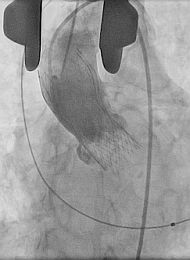

Medicos Argentinos realizan novedosa cirugía para reemplazar válvula cardíaca‏

Una paciente de 85 años se convirtió en la primera en el país en recibir una novedosa cirugía: un reemplazo de válvula aórtica a partir de la combinación de técnicas quirúrgicas y hemodinamia, empleando la...